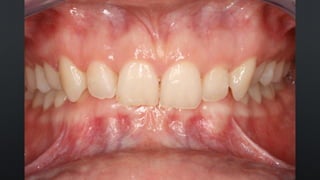

REABILITAÇÕES PROTÉTICAS

ORTODONTIA

TRATAMENTO DAS DTM`S

FORMATO DOS ARCOS RELAÇÃOINTERDENTAL RELAÇÃO ENTRE OS ARCOS RELAÇÃO DENTÁRIA INTRA- ARCO REABILITAÇÕES PROTÉTICAS ORTODONTIA TRATAMENTO DAS DTM`S